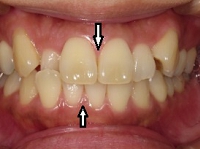

(その2)↑.

このケースは,下顎が横(右側)に大きくズレていて,上顎の歯並びに凸凹もみられます.

<治療経過>

.

↑スプリント療法と,マルチブラケット矯正を併用して治療を行いました.下顎にオクルーザルスプリントを使用しながら,上顎の歯列アーチの拡大および個々の歯の整列を行った結果,下顎の右方偏位は改善し,上下の歯列の正中はほぼ一致するようになりました.